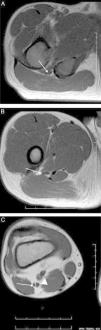

Magnetic resonance (MR) neurography refers to a set of techniques that enable the structure of the peripheral nerves and nerve plexuses to be evaluated optimally. New two-dimensional and three-dimensional neurographic sequences, in particular in 3T scanners, achieve excellent contrast between the nerve and perineural structures. MR neurography makes it possible to distinguish between the normal fascicular pattern of the nerve and anomalies like inflammation, trauma, and tumor that can affect nerves. In this article, we describe the structure of the sciatic nerve, its characteristics on MR neurography, and the most common diseases that affect it.